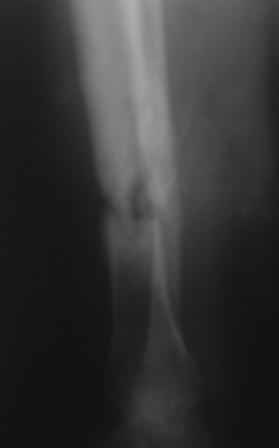

Добрый вечер, уважаемые коллеги! Обратилась женщина, 30 лет. ДТП 11 октября 2008 г. Из выписки: О/многооскольчатый перелом костей левой голени по Каплану 3В,

ПХО раны, гипсовая повязка, перевод в гор.б-цу, в 21.10.08г КДО аппаратом Илизарова(почему-то в вальгусном положении), ч-з два месяца тромбофлебит лев.н/конечности, отеки, воспаление, и аппарат сняли, с тех пор ходит в гипсовой повязке со стременем. к-рую периодически меняют, якобы кость со временем срастется.

На уровне н/з голени глубокие рубцы по передне-медиальной поверхности, умеренная отечность голени, незначительная патологическая подвижность, умерен. болезненность, ось правильная, укорочение 1,5см.

Наш план БИОС после остеоклазии м/берцовой кости. Но укорочение еще будет увеличиваться!